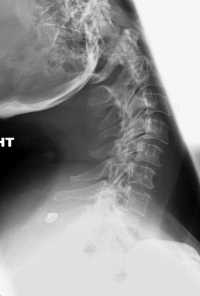

(Click to Enlarge Image) AP X-ray of severe degenerative facet disease that leads to instability. The white arrows point to the worn facets.